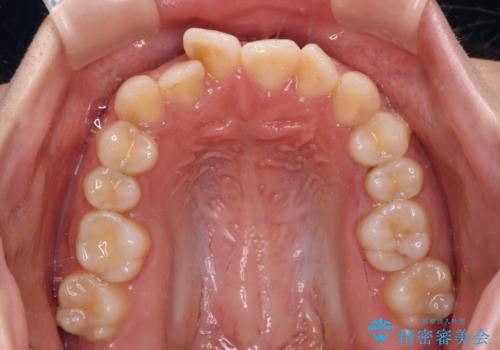

- 前歯のデコボコを気にして来院された患者様です。

マウスピース矯正のような自己管理の煩わしさがなく、早く治療を終えたいとのことで、ワイヤー装置による矯正治療を行うこととしました。